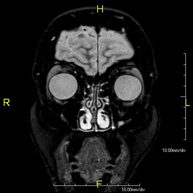

Prova diagnòstica no invasiva que consisteix en l'obtenció d'imatges d'alta definició anatòmica de les òrbites mitjançant l'ús d'un camp electromagnètic i ones de ràdio (amb un emissor i un receptor). No utilitza radiació ionitzant. Indicacions: visió doble, traumatisme, sospita de tumor, hipertiroïdisme. - RM d'Hipòfisi

Prova diagnòstica no invasiva que consisteix en l'obtenció d'imatges d'alta definició anatòmica de la hipòfisi cerebral mitjançant l'ús d'un camp electromagnètic i ones de ràdio (amb un emissor i un receptor). No utilitza radiació ionitzant. Indicacions: trastorn del creixement, trastorns hormonals, tumors. - RM de Sins paranasals

Prova diagnòstica no invasiva que consisteix en l'obtenció d'imatges d'alta definició anatòmica dels sins paranasals mitjançant l'ús d'un camp electromagnètic i ones de ràdio (amb un emissor i un receptor). No utilitza radiació ionitzant. Indicacions: estudi de tumors.